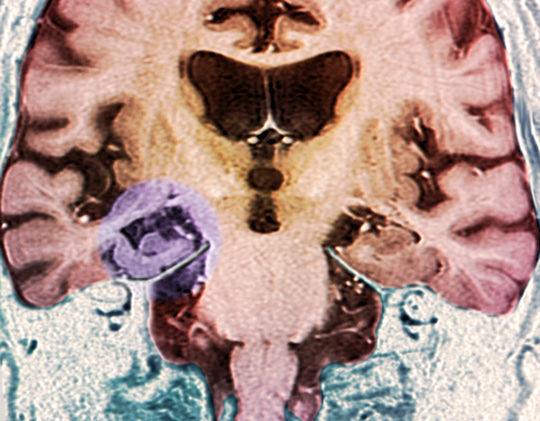

Farget MR-skann av koronal seksjon av hjerne og hjernestamme (nederst til venstre) hos en pasient med Alzheimers sykdom…

Farget MR-skann av koronal seksjon av hjerne og hjernestamme (nederst til venstre) hos en pasient med Alzheimers sykdom viser plakk i høyre hippocampus. Illustrasjon: Science Photo Library